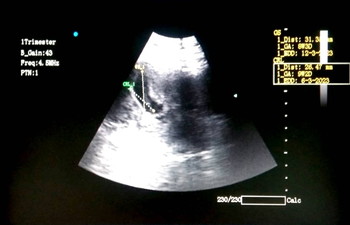

Di kehamilan anak ke 2 ini, aku rajin konsul dengan SpOG sejak di usia 7 minggu. Minus mataku sekarang 7.5. Khawatir pasti ada, tapi aku selalu berusaha berpikir yang positif saja.